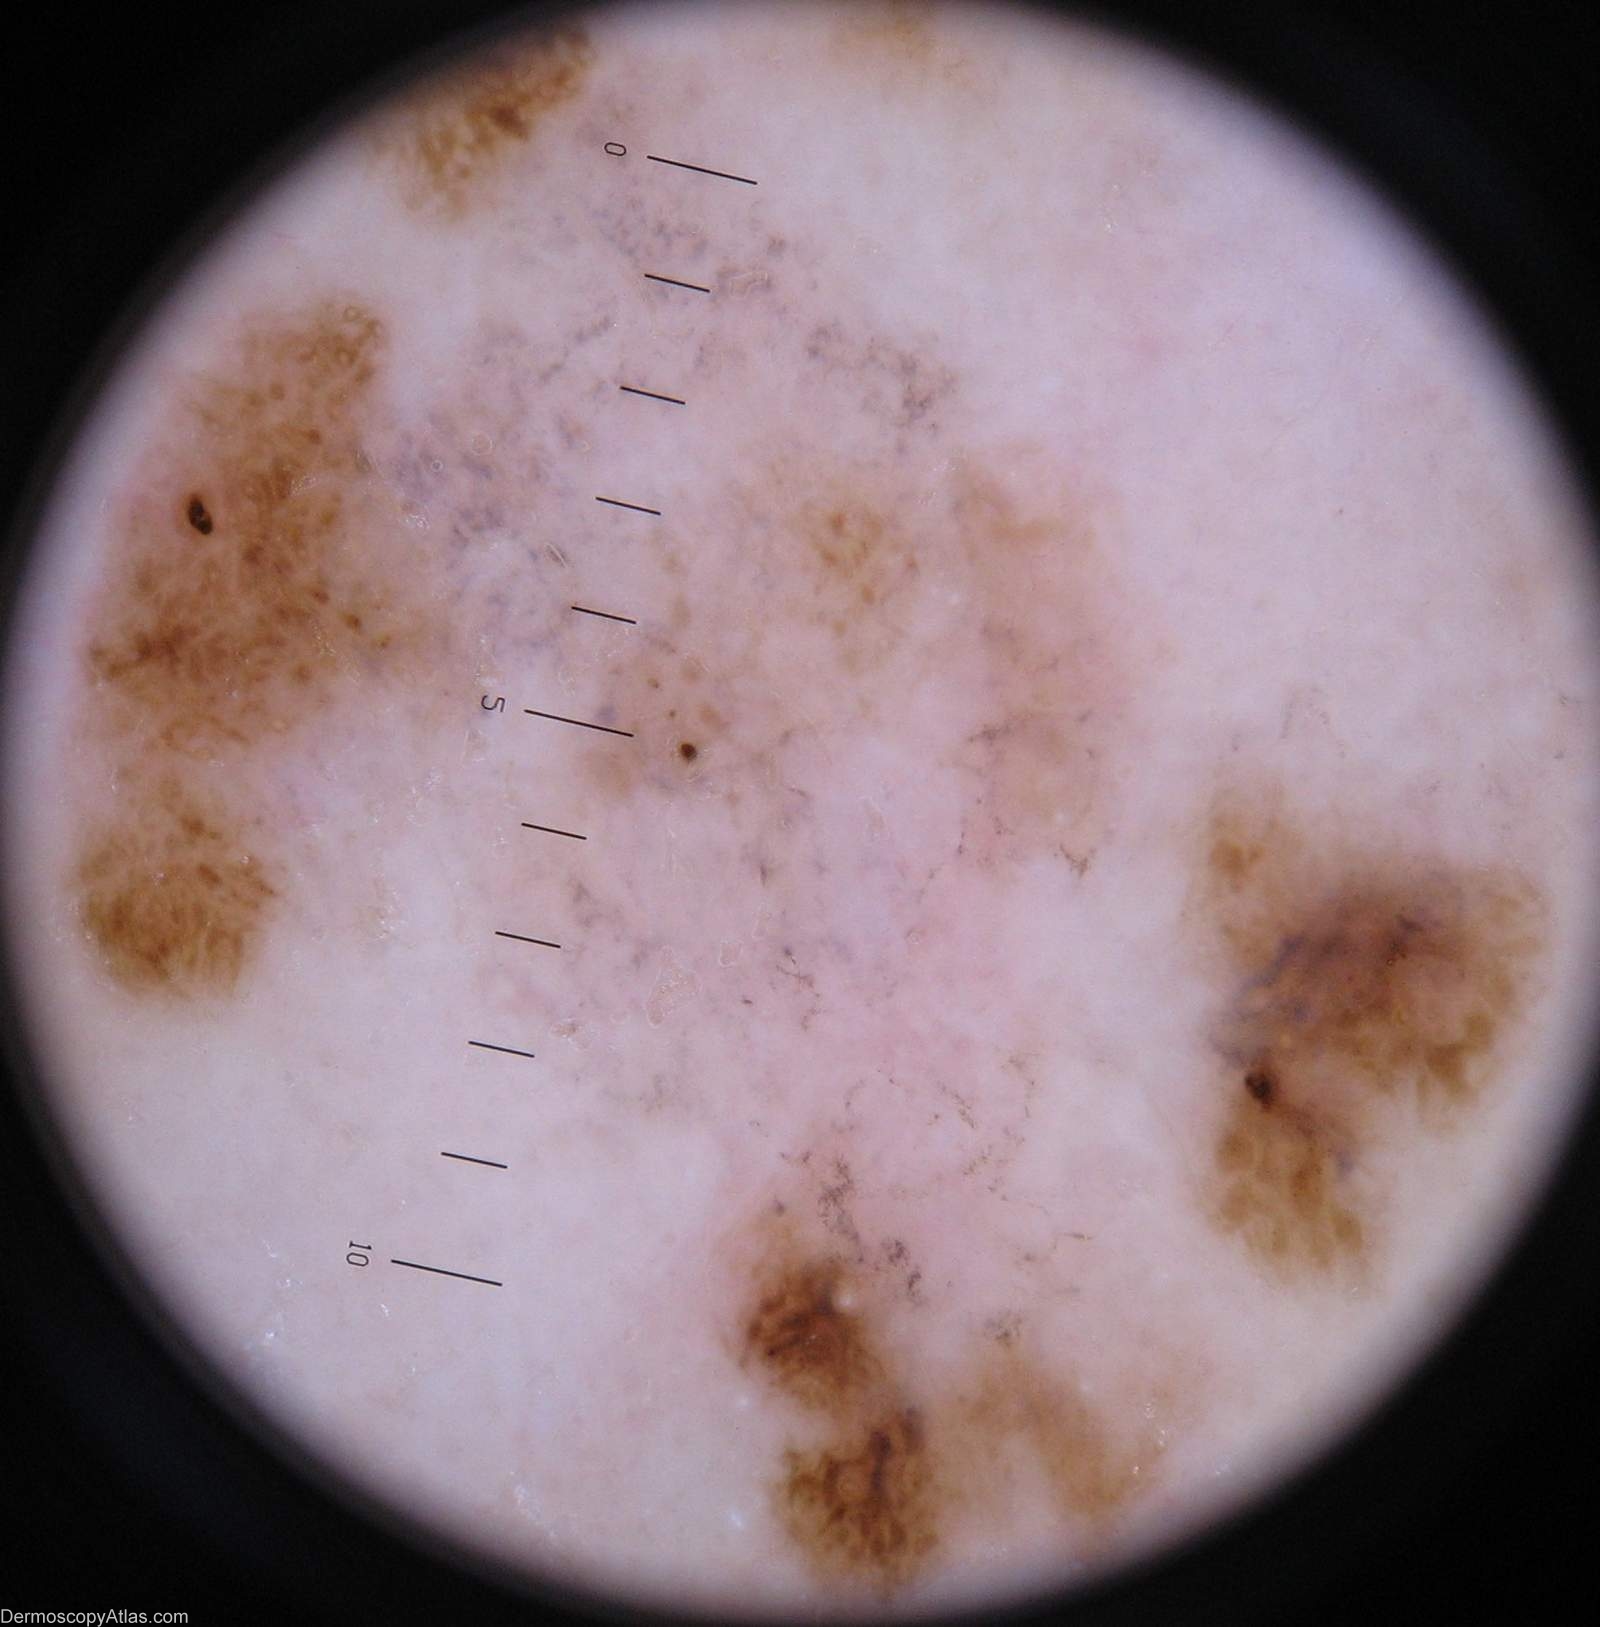

Diagnosis: Melanoma regression

Description: Lesion on the calf. Clinically areas of regression are shown in both the pale and grey areas

Case courtesy of Dr Greg Canning This poorly demarcated lesion is approx 5 cm in diameter and has resided on the left proximal postero medial calf of it's 72 year old owner for as long as she can remember. On reflection however she thinks it may have enlarged somewhat over the years. She has been repeatedly reassured about it by the doctors who have treated her numerous non melanoma skincancers.

Histopathology of incisional biopsy There is an atypical melanocytic lesion composed of disparate foci separated by zones of regression. There are moderately to markedly atypical melanocytes forming irregular junctional nests and invading the epidermis. A lichenoid dermal inflammatory infiltrate is present and there are two foci of superficial nvasion of the dermis to the interface of papillary and reticular dermis. The Breslow thickness in each case is 0.4 mm. Mitoses are rare. The minimum clearance of the invasive components is 2.5 mm from the 3 o'clock margin. Atypical junctional nests almost abut the 3 o'clock edge.

The degree of regression obfuscates interpretation of the precursor lesion, but lentiginous activity is seen and involvement of a hair follicle. In combination with the multifocal nature of the lesion it

is likely that this is lentigo maligna melanoma.